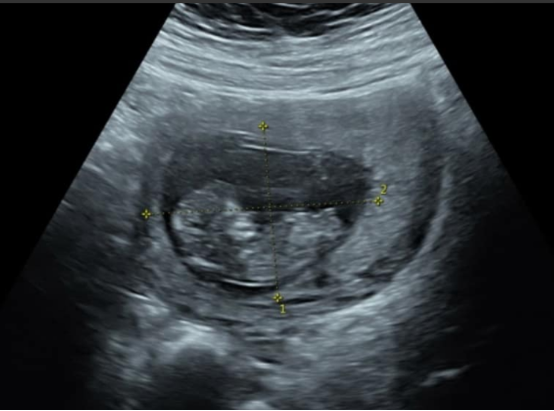

近日,据台媒报道,女星宣宣在打了200余针后终于如愿怀孕,目前已经5个月胎儿状况平稳,消息曝光后许多人也都纷纷祝愿宣宣能够顺利生下一个健康的孩子当上妈妈。

好在功夫不负有心人,宣宣终于在五个月前怀上了,而且这个宝宝长得十分健康,如果没有意外应该会顺利出生。看着打了这么多针肚皮都是一片淤青的宣宣,大家也都非常心疼她。